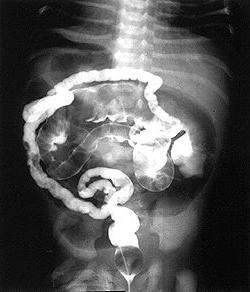

Иллюстрации и информация о симптомах острого кишечного непроходимости